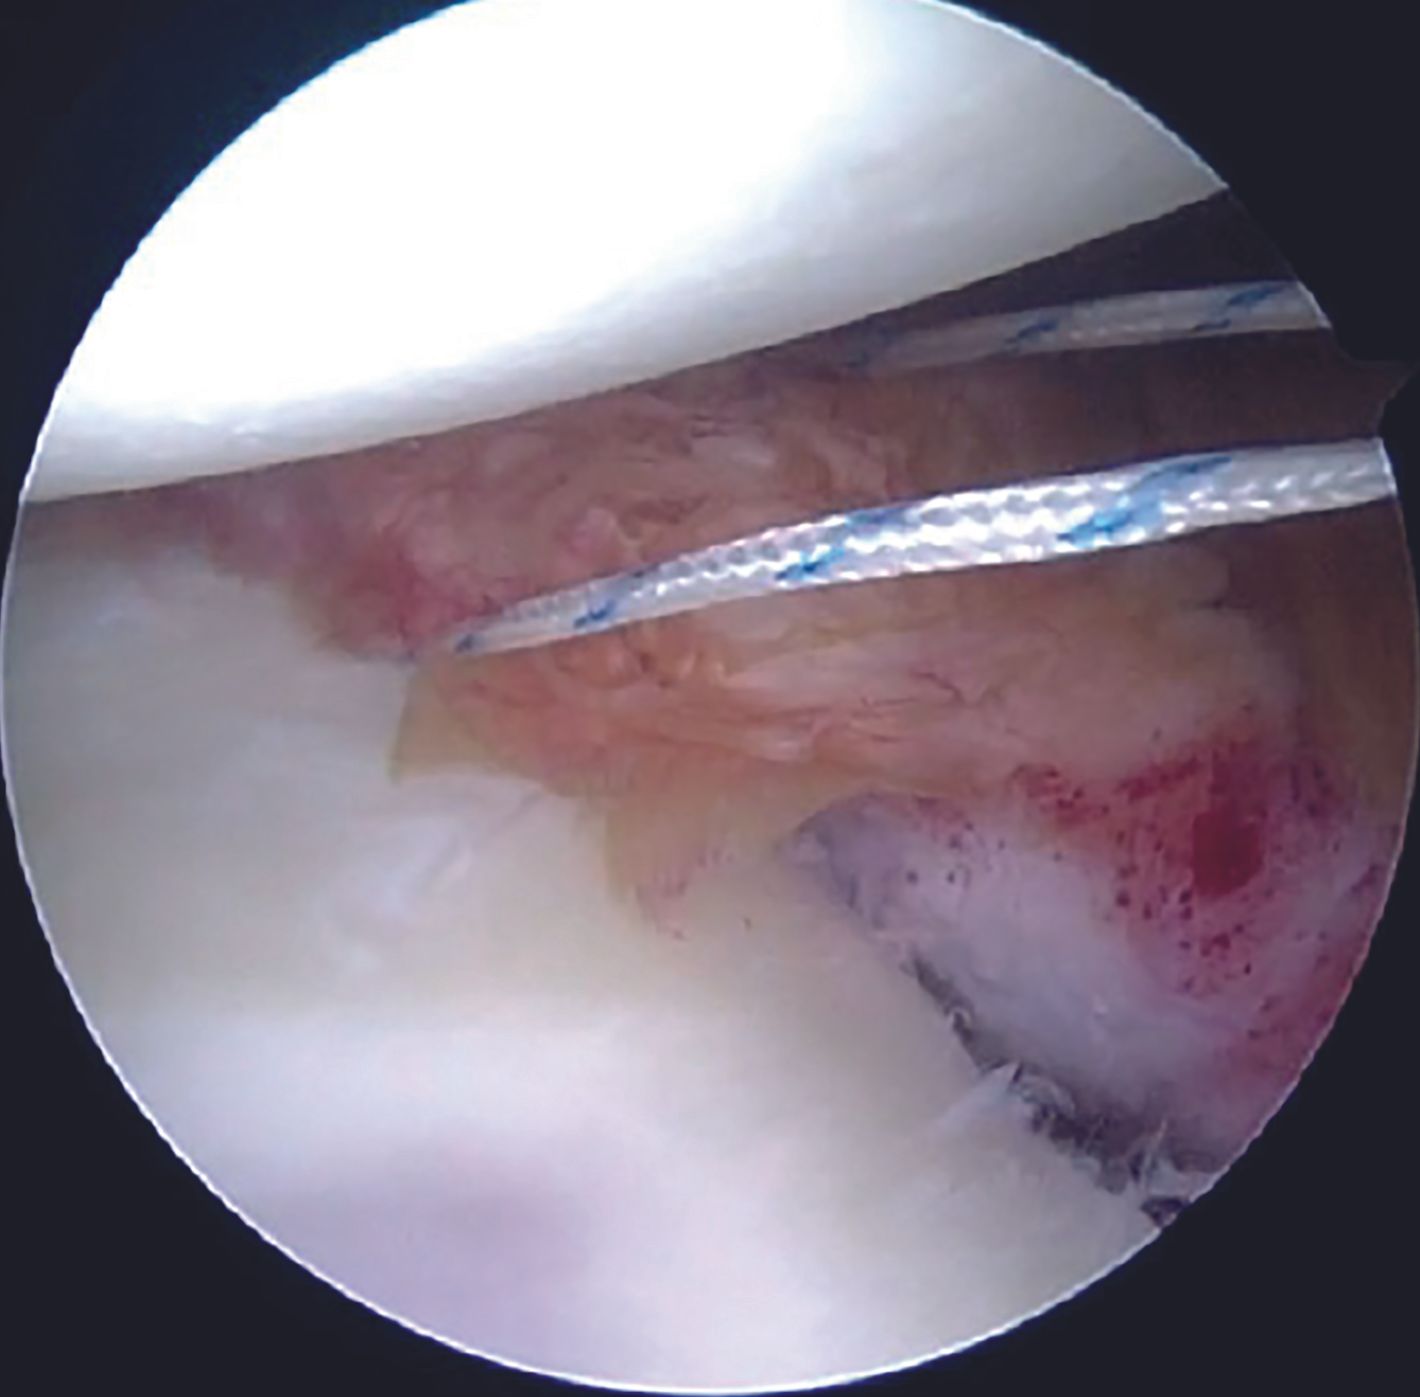

A grasper can be utilized for holding the labral tissue in order to allow easy passage of the suture passer device. With both the tapes in the AI portal, a sliding Duncan loop knot is first tied (Figure 14), followed by at least three half hitches.

Care is taken to keep the knots away from the face of the glenoid by using the shuttled tape as a post and the other one as a throw. Before tying the sliding knot, utmost attention should be paid to provide adequate tension to the labral tissue by pulling the labrum superiorly with a grasper. Tapes are cut with an arthroscopic cutter around 4 to 5mm distal to the knot. One anchor each is placed at 4 and then at 3 O'clock position following a similar steps. After completion of the repair (Figure 15, 16), its integrity and stability is confirmed with a probe. After a thorough wash, closure is done with mattress sutures using 3-0 Ethilon.